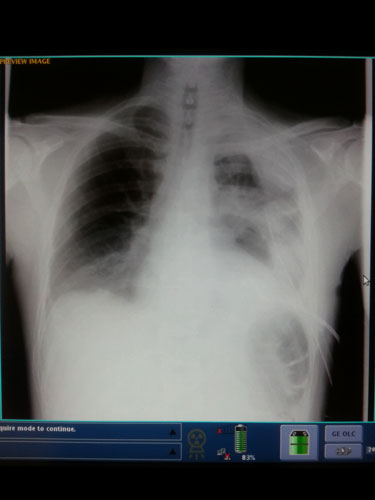

Square Peg kept me posted with texts as I drove the longest 20 miles of my life to get home in traffic. When the ambulance left our place she went with him and kept me posted. I got off the freeway and started heading to the hospital. I beat the ambulance to the hospital by just a few minutes and was waiting in the emergency room area for him. Mike could not breathe. He was in excruciating pain and was breathing fast. In the emergency room they loaded him up on morphine. The morphine made him delusional but did not help with his pain or breathing. Our friends CB (who was a military medic) and other friend Cheeky came out to offer support. CB and Square Peg helped to keep Mike focused on taking slower fuller breaths. They also helped to keep me calm as I was a nervous frantic wreck. X-rays were taken and the nurse told me it was pneumonia and they were going to send Mike home that night. I could not believe it! He could barely breath and was in so much pain that he was ready to die. I was so grateful to have Square Peg, CB, and Cheeky there with me because they helped me deal with the medical staff and they told me “they can’t make you take him home tonight. You keep asking for another opinion. They should at least keep him overnight for observation.”

After 4 hours in the emergency room the doctor finally ordered a CT scan and they discovered it wasn’t pneumonia. His chest was full of fluid compressing one of his lungs more and more with every breath. They immediately popped him like a juice box and installed a chest drain to get the fluid out. Over a liter of fluid drained in the first hour. The doctors still didn’t know exactly what was wrong with Mike though. It was first diagnosed as pneumonia, then chest trauma due to roller derby before it was finally correctly diagnosed as Boerhaaves Syndrome.